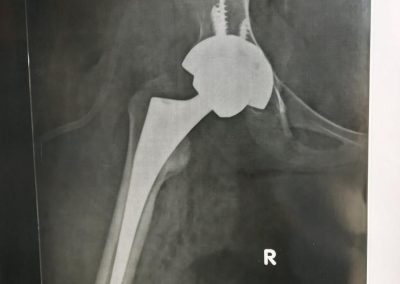

الاشعه بعد الجراحة تبين المفصل الصناعي الجديد مع تعويض تام للقصر.